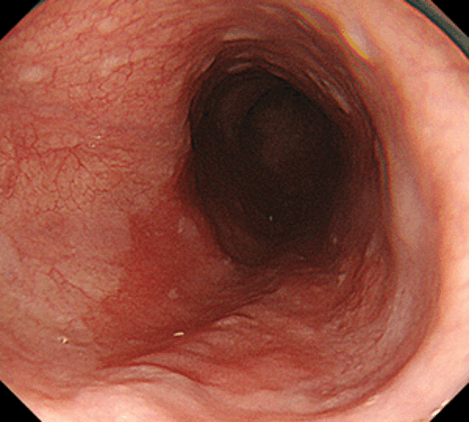

食道の粘膜の表面は、胃や大腸の粘膜表層を構成する腺上皮とは異なり、皮膚・口腔・肛門管と同様の重層扁平上皮で覆われています。その食道粘膜表層の重層扁平上皮ががん化することで発生する悪性腫瘍が、典型的な食道がんとされている扁平上皮がんです。本邦の食道がんの9割弱は扁平上皮がんであるとされています(残りのほとんどはバレット腺がん)。早期の食道がんや表在型食道がんにおいては症状がほとんどないため、内視鏡検査によってたまたま見つかることがある一方で、発見が遅れて進行してから見つかるケースも少なくありません。

食道がん(扁平上皮がん)